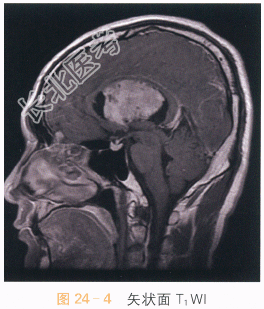

影像学资料如图24-1~图24-4所示。

读片分析:头颅MRI检查横断面T₂-Flair可见左侧侧脑室及透明隔区不规则软组织肿块,呈等高信号影,病灶内可见小片状囊变影,左侧侧脑室扩大,右侧侧脑室受压;增强扫描可见片状不均匀明显强化,囊变区无明显强化。结合患者病史,可考虑诊断为中央神经细胞瘤。